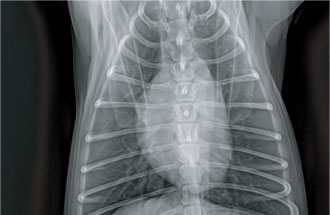

방사선 검사 (철사 이물 확인)